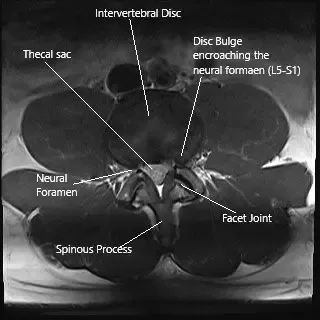

Axial section of the spine at L5-S1 level on an MRI

The pain is due to a combination of inflammation and decreased blood supply to the nerve root commonly known as a nerve root irritation. The most common cause of this irritation is disc herniation. Other uncommon causes can be facet arthritis and synovial cyst.